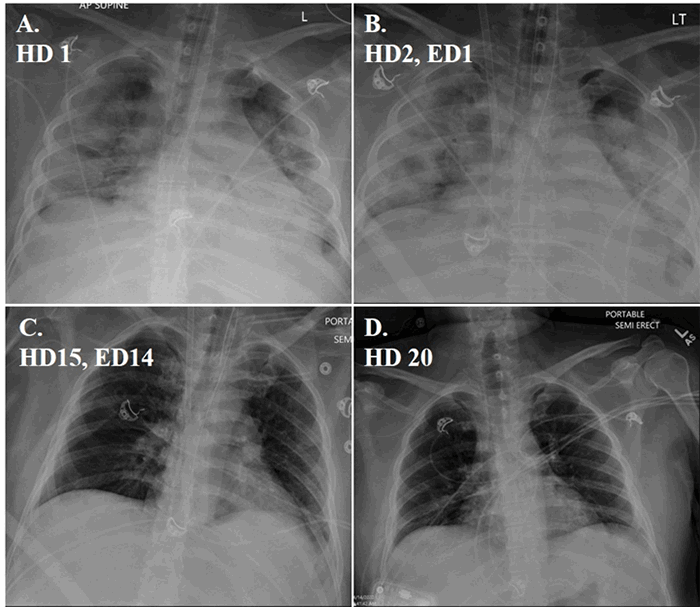

Ultrasound-guided vascular access was performed using the Seldinger technique. VV-ECMO cannulation was performed utilizing a 17F short Bio-Medicus return cannula in the right internal jugular vein and a 25F Medtronic right common femoral venous drainage cannula. Once the cannulas were connected to the ECMO circuit, the CentriMag pump achieved 5 L/min flow and oxygen saturations of 100 percent. We maximized ECMO support with 100 percent FiO2 and 8L/min sweep for 24 hours. Our ventilator management followed the EOLIA trial protocol2 with full sedation and paralysis. A seven-day course of hydroxychloroquine and five-day course azithromycin was given. Unfortunately, the patient experienced acute kidney injury requiring renal replacement therapy on the fourth postoperative day. On full ECMO support, we made slow progress weaning the ventilator until postoperative day nine. Once our ventilator requirements reached 40 percent FiO2, we weaned our ECMO oxygenation and sweep. Convalescent serum was administered on postoperative day 12 and paralytics were held. Once off paralytics, our patient demonstrated improving tidal volumes on pressure control ventilator settings, and his oxygenation continued to improve. His sweep wean was rapid once his oxygenation and chest X rays had improved. On postoperative day 14, the patient was successfully decannulated from ECMO. By postoperative day 16, he was extubated, and by postoperative day 18, he was on clinically stable on room air. Serial chest X rays of his recovery are demonstrated in Figure 1.

Figure 1. Serial CXR of SARS-Cov2 pneumonia recovery. (A) Hospital Day (HD) 1; (B) HD 2, ECMO Day (ED) 1; (C) HD 15, ED 14, day of decannulation; (D) HD 20.